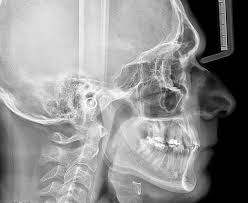

๐—ฆ๐—ถ ๐˜๐˜‚ ๐—ฝ๐—ฎ๐—ฐ๐—ถ๐—ฒ๐—ป๐˜๐—ฒ ๐—ฟ๐—ฒ๐˜€๐—ฝ๐—ถ๐—ฟ๐—ฎ ๐—ฝ๐—ผ๐—ฟ ๐—น๐—ฎ ๐—ฏ๐—ผ๐—ฐ๐—ฎ, ๐˜๐˜‚ ๐—ฒ๐˜…๐—ฝ๐—ฎ๐—ป๐˜€๐—ถรณ๐—ป ๐—ฟ๐—ฒ๐—ฐ๐—ถ๐—ฑ๐—ถ๐˜ƒ๐—ฎ๐—ฟรก. ๐Ÿ˜ค๐Ÿšฉ Soy la @Dra. Marta Cuadra y este es un punto crรญtico en la visiรณn funcional. Un respirador bucal suele tener una arcada comprimida, un paladar ojival y una mandรญbula retrognรกtica. La lengua nunca estรก en el paladar, por lo que no hay estรญmulo expansivo natural. Como arquitecta de sonrisas, antes de dar el "Approve" a un ClinCheck expansivo, me aseguro de que el paciente ha pasado por el otorrino o que estamos trabajando la respiraciรณn nasal. Si no corriges la causa aรฉrea, el plรกstico no podrรก luchar contra la presiรณn negativa constante de las mejillas. Hablemos de diagnรณstico: 1. ยฟ๐—ง๐—ฒ ๐—ณ๐—ถ๐—ท๐—ฎ๐˜€ ๐—ฒ๐—ป ๐—น๐—ฎ ๐—ฝ๐—ผ๐˜€๐—ถ๐—ฐ๐—ถรณ๐—ป ๐—ฑ๐—ฒ ๐—น๐—ผ๐˜€ ๐—น๐—ฎ๐—ฏ๐—ถ๐—ผ๐˜€ ๐—ฒ๐—ป ๐—ฟ๐—ฒ๐—ฝ๐—ผ๐˜€๐—ผ ๐—ฑ๐—ฒ ๐˜๐˜‚๐˜€ ๐—ฝ๐—ฎ๐—ฐ๐—ถ๐—ฒ๐—ป๐˜๐—ฒ๐˜€? 2. ยฟ๐—–๐—ผ๐—น๐—ฎ๐—ฏ๐—ผ๐—ฟ๐—ฎ๐˜€ ๐—ฐ๐—ผ๐—ป ๐—ผ๐˜๐—ผ๐—ฟ๐—ฟ๐—ถ๐—ป๐—ผ๐—น๐—ฎ๐—ฟ๐—ถ๐—ป๐—ดรณ๐—น๐—ผ๐—ด๐—ผ๐˜€ ๐—ฒ๐—ป ๐˜๐˜‚ ๐—ฝ๐—น๐—ฎ๐—ป๐—ถ๐—ณ๐—ถ๐—ฐ๐—ฎ๐—ฐ๐—ถรณ๐—ป? 3. ยฟ๐—–รณ๐—บ๐—ผ ๐—ต๐—ฎ๐—ฐ๐—ฒ๐˜€ ๐—พ๐˜‚๐—ฒ ๐—ฒ๐—น ๐—ฝ๐—ฎ๐—ฐ๐—ถ๐—ฒ๐—ป๐˜๐—ฒ ๐˜€๐—ฒ๐—ฎ ๐—ฐ๐—ผ๐—ป๐˜€๐—ฐ๐—ถ๐—ฒ๐—ป๐˜๐—ฒ ๐—ฑ๐—ฒ ๐—พ๐˜‚๐—ฒ ๐˜€๐˜‚ ๐—ฝ๐—ฟ๐—ผ๐—ฏ๐—น๐—ฒ๐—บ๐—ฎ ๐—ฒ๐˜€ ๐—ฟ๐—ฒ๐˜€๐—ฝ๐—ถ๐—ฟ๐—ฎ๐˜๐—ผ๐—ฟ๐—ถ๐—ผ? #RespiracionBucal #OrtodonciaFuncional #DraMartaCuadra #SaludIntegral #ClinCheckTips